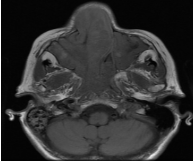

El diagnóstico diferencial de papiloma invertido y otras masas de la fosa nasal es de difícil determinación, siendo necesaria las mediciones densitométricas tomográficas. Los valores densitométricos de la masa en las adquisiciones en nuestro paciente sin contraste se encuentran entre 55 - 60 UH y posterior a la infusión del contraste oscila entre 70 - 80 UH; el cornete medio presenta densidades entre 40 - 45 UH, mientras que las secreciones mucosas muestran valores entre 25 - 40 UH. Si bien estos realces no son específicos para realizar el diagnóstico de papiloma invertido, podrían ser de utilidad para la valoración de la extensión del mismo (Figura 1 – 2).

En la Tomografía sin contraste del macizo cráneo facial se aprecia formación de densidad de partes blandas ubicada en fosa nasal y seno maxilar derecho con extensión a senos frontales y celdillas etmoidales, la formación hace protrusión hacia las coanas y Cavum con marcado realce postcontraste (Figura 3).